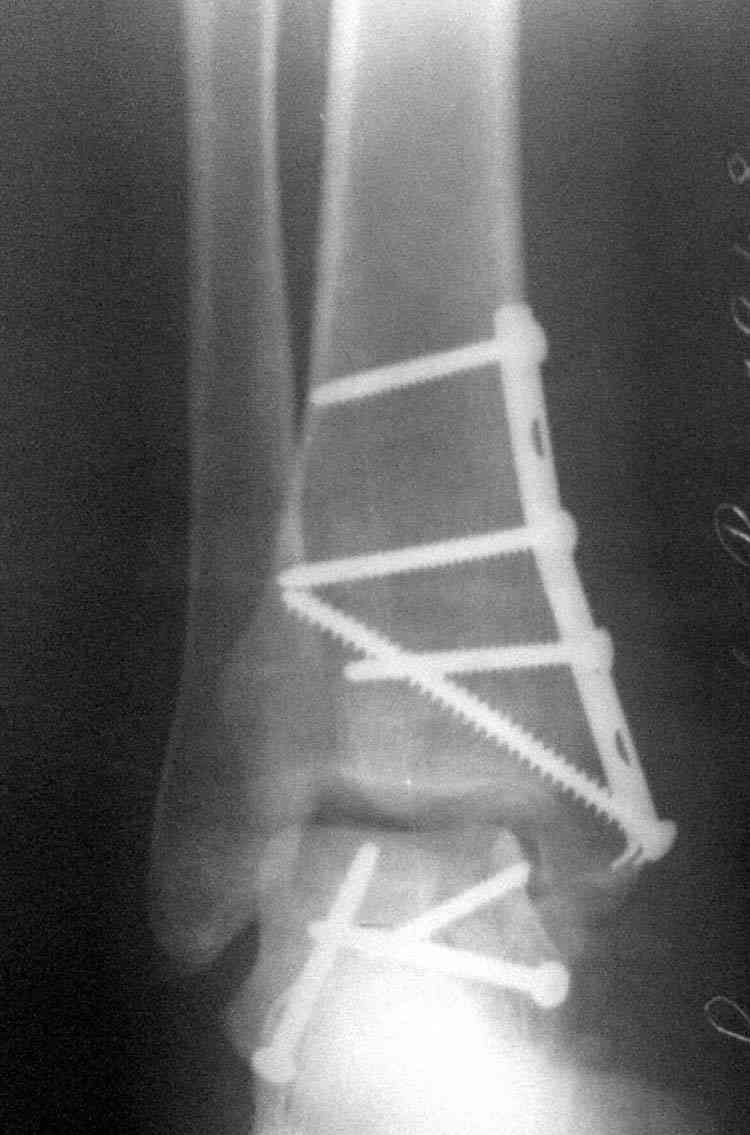

Случай с множественным оскольчатым переломом тарана оперированный из двойного доступа.

Через 8 мес.:

(кстати, на нашем случае была применена костная пластика-allograft crouton для заполнения дефектов)